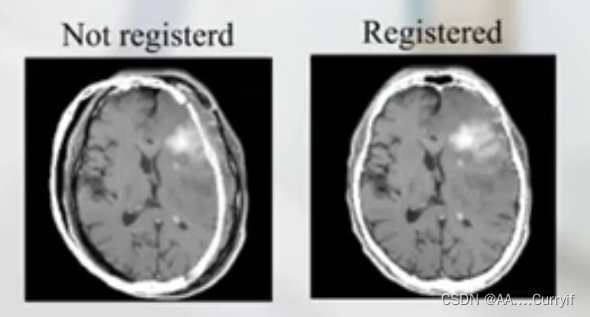

六、可视化(Visualization)

-Color overlay(彩色叠加,实现差异的变化)

-Interleaved pixel or chessboard fusion(将两幅图像切成小方块,在他们相邻的方块之间显示不同的图像,通过方块之间的衔接,判断配准是否准确)

-Dynamic alternating display

-Split view displays(两个显示器)

-Subtraction images(做减法)